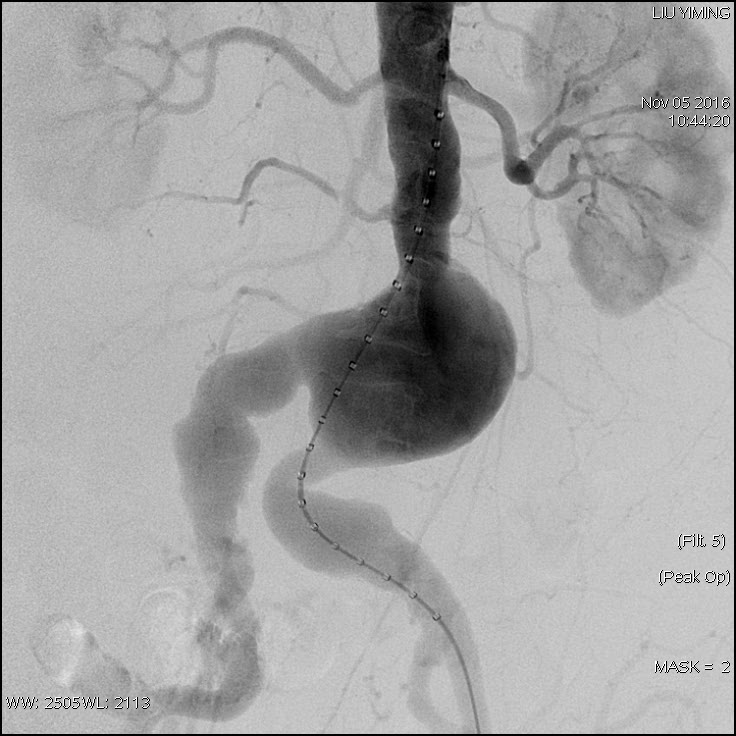

其中,在复杂主动脉病变腔内修复术应用手术直播中,郭伟教授带领其团队使用彩神在线网信彩票-彩神通免费版下载-彩神8争霸vlll-彩神购彩购彩大厅-彩神软件陆立根免费版-彩神ll争霸3-彩神ll彩神8-彩神ll争霸彩票-拼搏在线彩神网网页版科技公司的髂动脉分叉支架系统(IBD)以完全腔内重建的方式成功修复复杂腹主动脉瘤及髂动脉瘤。该例手术患者为64岁的男性,被诊断为肾下腹主动脉瘤,瘤体最大直径约6.5cm,双侧髂动脉瘤。患者成功植入彩神在线网信彩票-彩神通免费版下载-彩神8争霸vlll-彩神购彩购彩大厅-彩神软件陆立根免费版-彩神ll争霸3-彩神ll彩神8-彩神ll争霸彩票-拼搏在线彩神网网页版科技IBD支架,定位准确,无内漏,成功保留了左侧髂内动脉,术后造影显示髂内动脉通畅。

图:术前造影、术中造影、术后造影